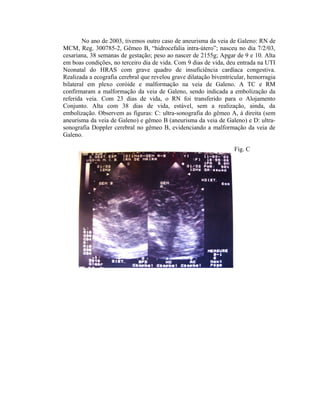

No ano de 2003, tivemos outro caso de aneurisma da veia de Galeno: RN de

MCM, Reg. 300785-2, Gêmeo B, “hidrocefalia intra-útero”; nasceu no dia 7/2/03,

cesariana, 38 semanas de gestação; peso ao nascer de 2155g; Apgar de 9 e 10. Alta

em boas condições, no terceiro dia de vida. Com 9 dias de vida, deu entrada na UTI

Neonatal do HRAS com grave quadro de insuficiência cardíaca congestiva.

Realizada a ecografia cerebral que revelou grave dilatação biventricular, hemorragia

bilateral em plexo coróide e malformação na veia de Galeno. A TC e RM

confirmaram a malformação da veia de Galeno, sendo indicada a embolização da

referida veia. Com 23 dias de vida, o RN foi transferido para o Alojamento

Conjunto. Alta com 38 dias de vida, estável, sem a realização, ainda, da

embolização. Observem as figuras: C: ultra-sonografia do gêmeo A, à direita (sem

aneurisma da veia de Galeno) e gêmeo B (aneurisma da veia de Galeno) e D: ultra-sonografia

Doppler cerebral no gêmeo B, evidenciando a malformação da veia de

Galeno.

Fig. C